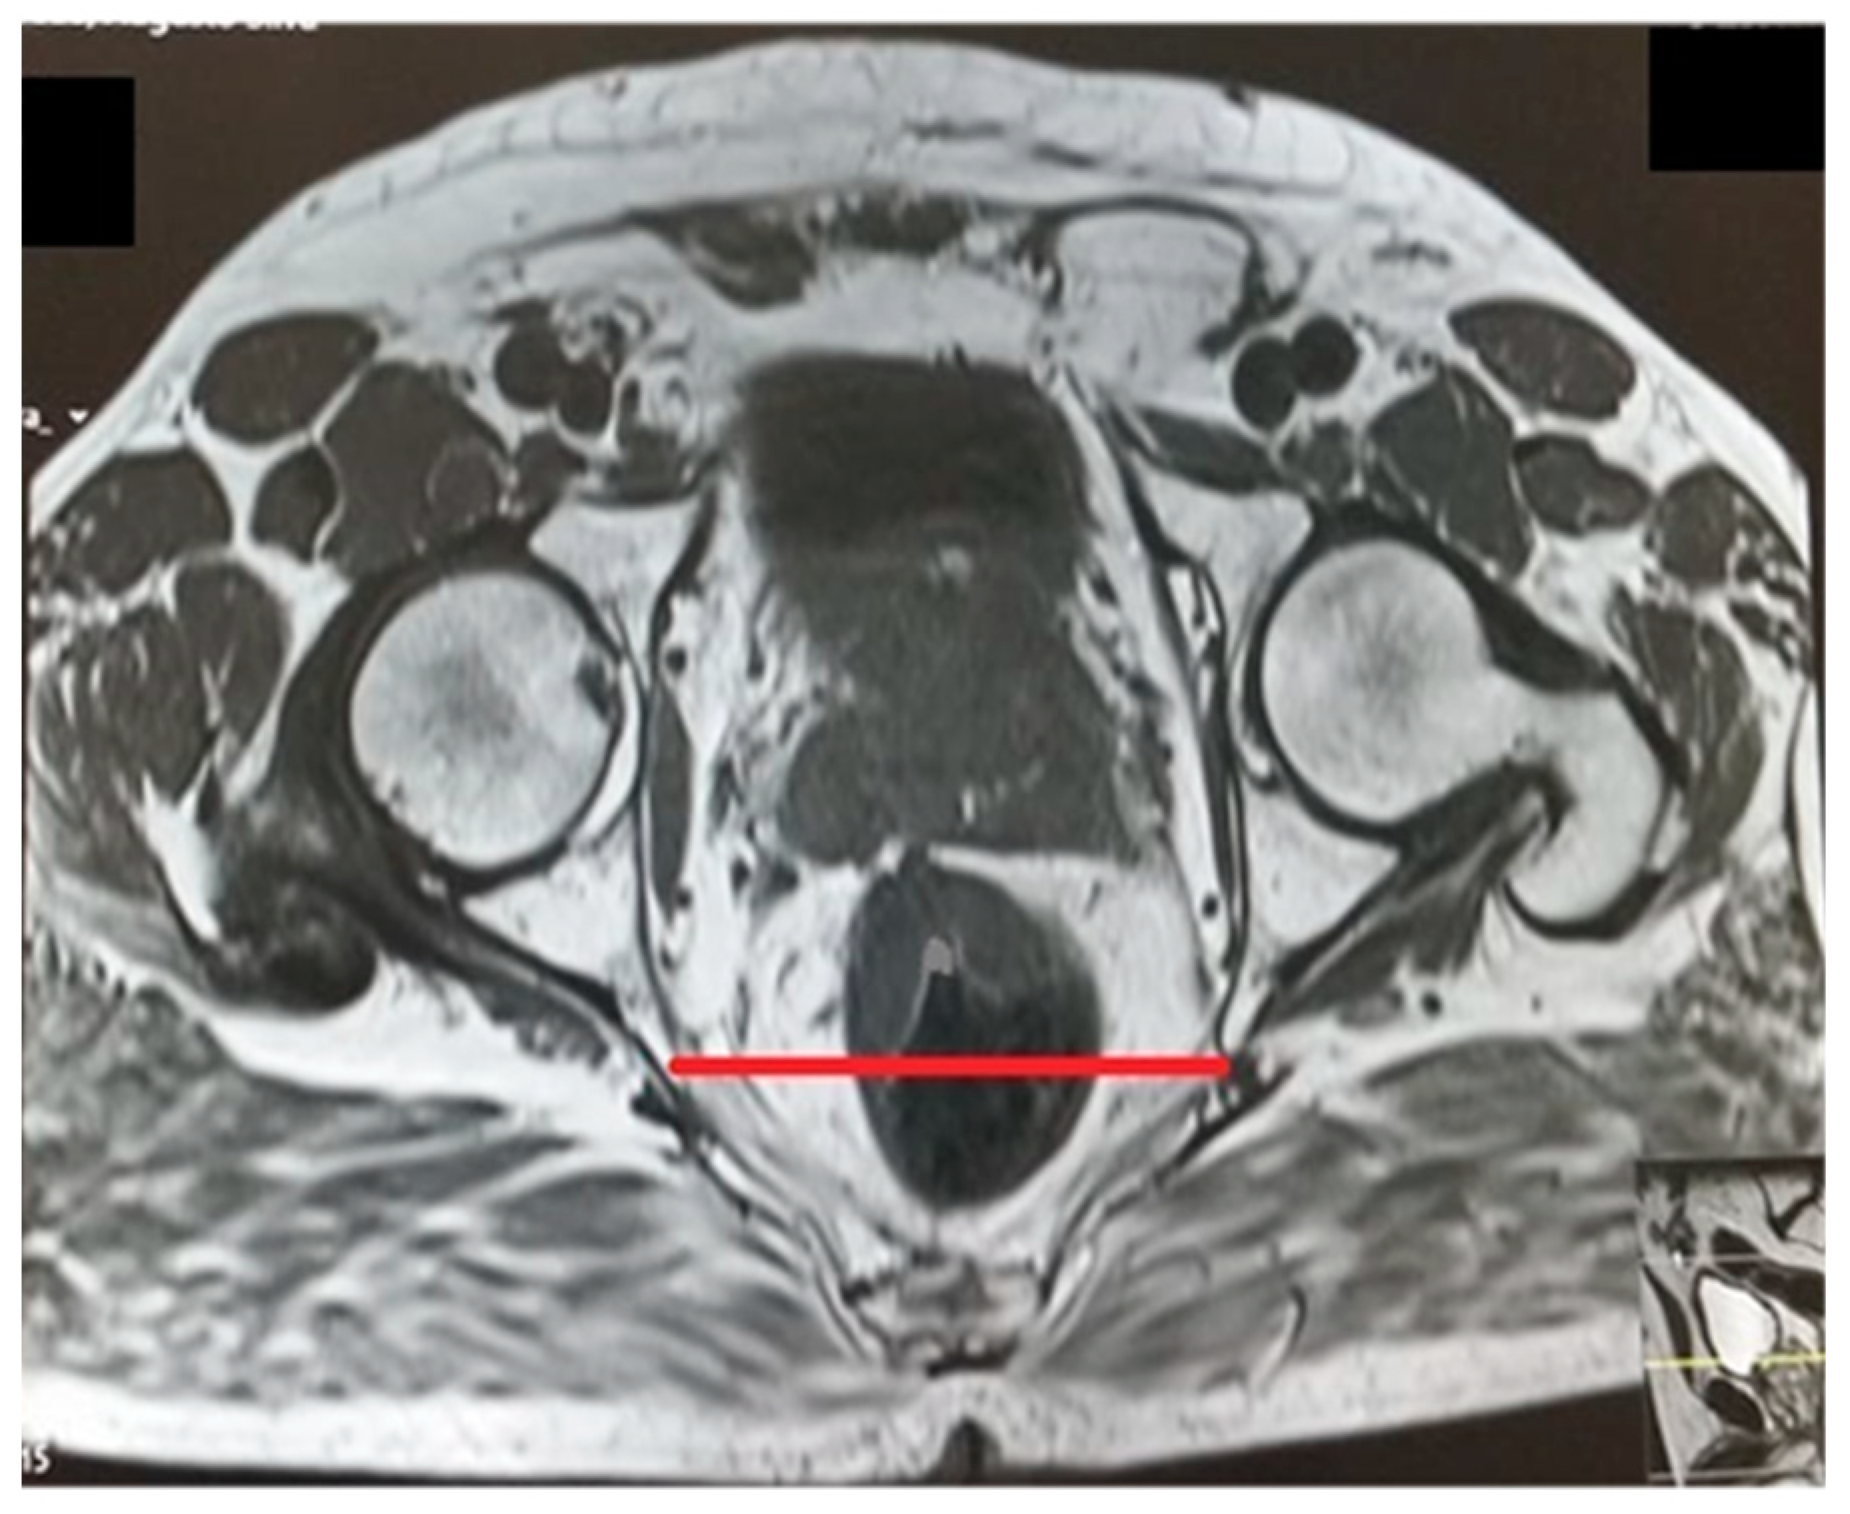

Figure 4.

Interspinous distance.